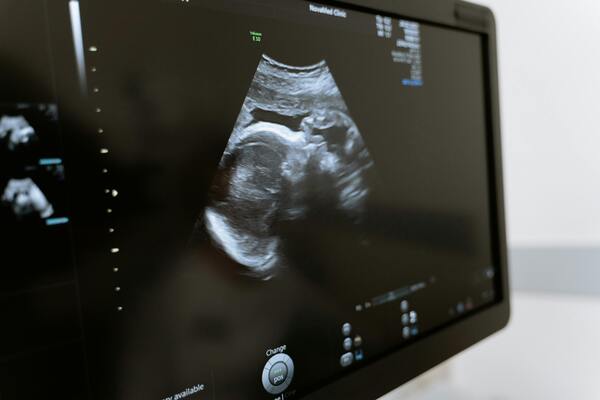

Quando a gravidez envolve riscos para a mãe ou o bebê, o papel do obstetra se torna ainda mais crucial. Esse profissional acompanha a gestante desde o início, identificando possíveis complicações como pré-eclâmpsia, diabetes gestacional e parto prematuro. O obstetra atua na prevenção, diagnóstico e tomada de decisões rápidas para garantir um desfecho saudável. No pré-natal, parto e puerpério, ele cuida da saúde física e emocional da mulher. Acesse o conteúdo completo e saiba mais sobre a importância do acompanhamento especializado: Gravidez de alto risco – Drauzio Varella.